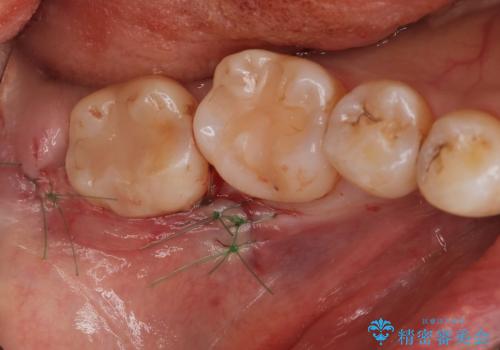

パノラマ,CT撮影を行い安全なことを確認して抜歯を行いました。

抜歯後1週間後に抜糸と消毒を行い処置は完了になります。